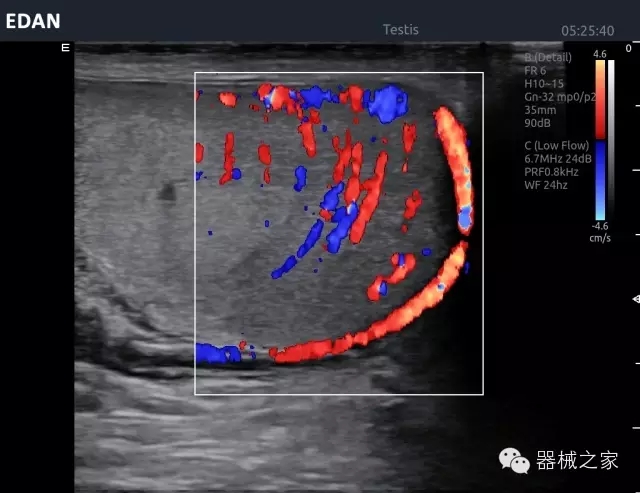

品牌:理邦儀器(EDAN)

經(jīng)典產(chǎn)品:Acclarix AX8

臨床圖片賞析

睪丸低速血流

臍帶血流

頸動脈頻譜